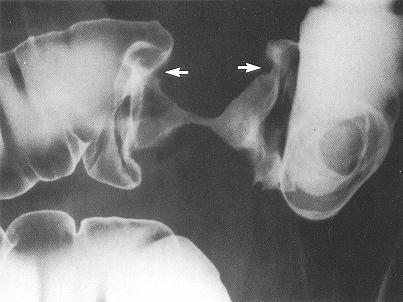

Several other tests are ordered: a cystogram shows the bladder intact but elongated and displaced to the right by the hematoma;

a venogram shows no damage to the left femoral or iliac veins.